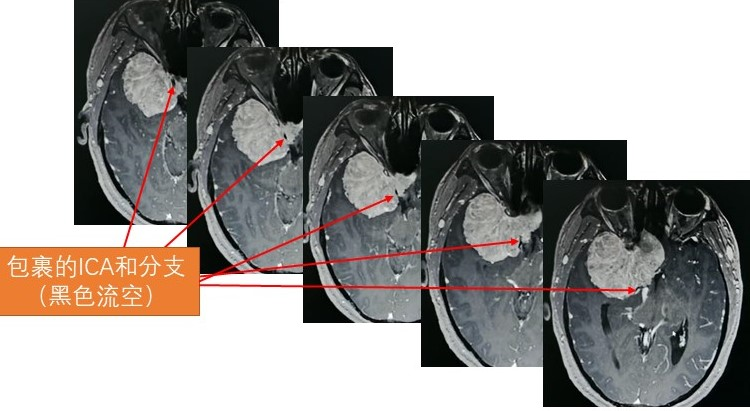

病例介绍

01

02

03

04